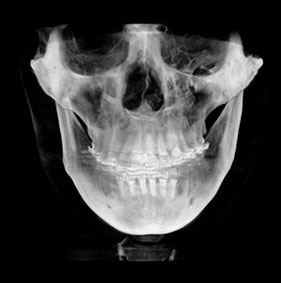

3D CT분석을 통한

정확한 코 재수술

원인 분석

코 재수술은 문제의 원인을

정확한 파악하는 것이 중요합니다.

V브이성형외과의

코성형 전담 의료진은

환자와 면밀한 상담을 통해서

현재 불만족의 원인을 파악하고

개선을 위한 방법을 모색합니다.

3D CT 분석을 통해서 해부학적인 상태를 확인하고,

기존 코수술로 인한 문제를 파악할 수 있습니다.